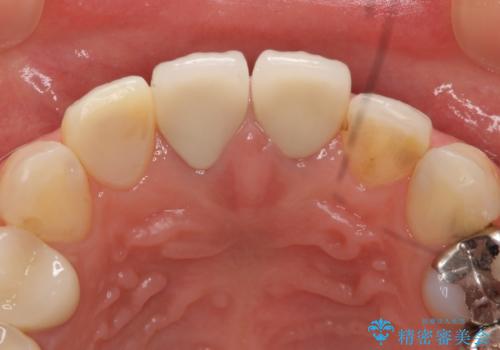

- 上顎の前から2番目の歯の古い樹脂をセラミックにしたいといらっしゃった方の症例です。

古い樹脂を除去後、オールセラミッククラウンによる補綴を行いました。